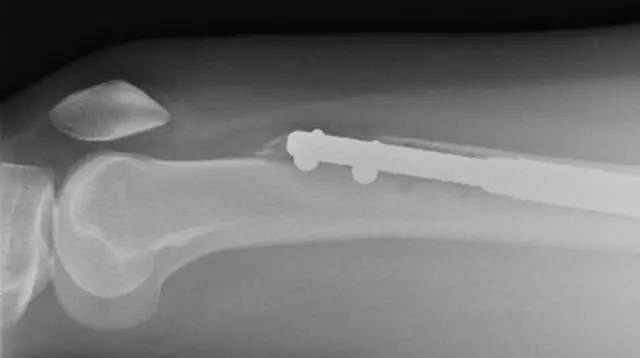

ఈ ప్రొసీజర్లో కొంత నొప్పి ఉంటుందని ఊహించాం. కానీ, ఆపరేషన్ సమయంలో కాళ్ల ఎముకలు రెండుగా చీల్చారు. లోహపు కడ్డీలు లోపల పెట్టారు.

ఈ లోహపు కడ్డీలు వాటి పొడవును పెంచుకునేందుకు క్రమంగా విస్తరిస్తాయి. ఈ సమయంలో ఎముక రెండు భాగాలు వేరువేరుగా అవుతాయి. ఈ ప్రక్రియ మెల్లగా రోగి ఎత్తును పెంచేందుకు ఉపయోగపడుతుంది. విరిగిన ఎముకలు తిరిగి క్రమంగా అతుక్కోవాలి. వాటి మధ్యలో ఉన్న గ్యాప్ను పూడ్చుకోవాలి. ఈ ఆపరేషన్ చాలా క్లిష్టమైంది.

ఎలైన్ స్కాన్ కోసం వెళ్లినప్పుడు తన ఎడమ కాలిలోని లోహపు కడ్డీ ముక్క ఆమె తొడ ఎముక నుంచి విరిగిపోయిందని తెలిసింది. మనిషి శరీరంలో అత్యంత బలమైన ఎముక తొడ ఎముకే.